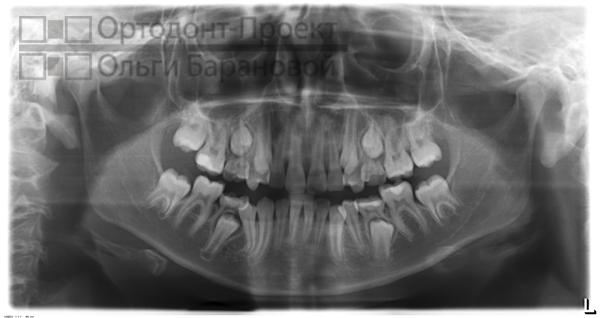

В начале лечения врач назовет примерные сроки и стоимость, которую определяет выбранная брекет-система. Он также предупредит о возможных сложностях, которые будут уточнены после детальной диагностики. Специалист расскажет, какие обследования нужно пройти, как будет проходить процесс исправления прикуса с помощью брекетов и какие шаги предстоит сделать. Если пациент согласен на лечение, врач предоставляет подробный план дальнейших действий. Пациенту требуется пройти фотометрию, сделать панорамный снимок зубов, слепки, ТРГ в боковой проекции и посетить остеопата и гигиениста.

Панорамный снимок зубов до начала курса лечения:

Врач-ортодонт поставил диагноз: скученность зубов на верхней челюсти. Рекомендуется установка брекет-системы Damon, которая отличается наличием двух пазов в замке брекета. На одной из стадий терапии доктор применит две дуги: первая будет отвечать за движение клыков, а вторая – за фиксацию резцов, чтобы избежать их смещения под воздействием клыков. Металлические брекеты Damon представляют собой современное и оптимальное решение. Их главные преимущества заключаются в доступной цене, компактных размерах и высокой эффективности, при условии правильного расчёта со стороны врача.